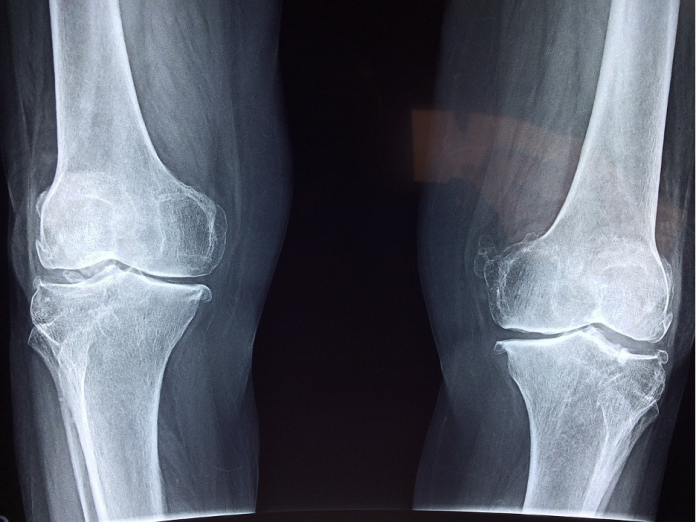

Orthopedics is the science of studying everything related to bones and fractures.

Bone fractures

In general, some bones are more susceptible to get broken than others; this is especially important for athletes and those with medical conditions, such as osteoporosis.